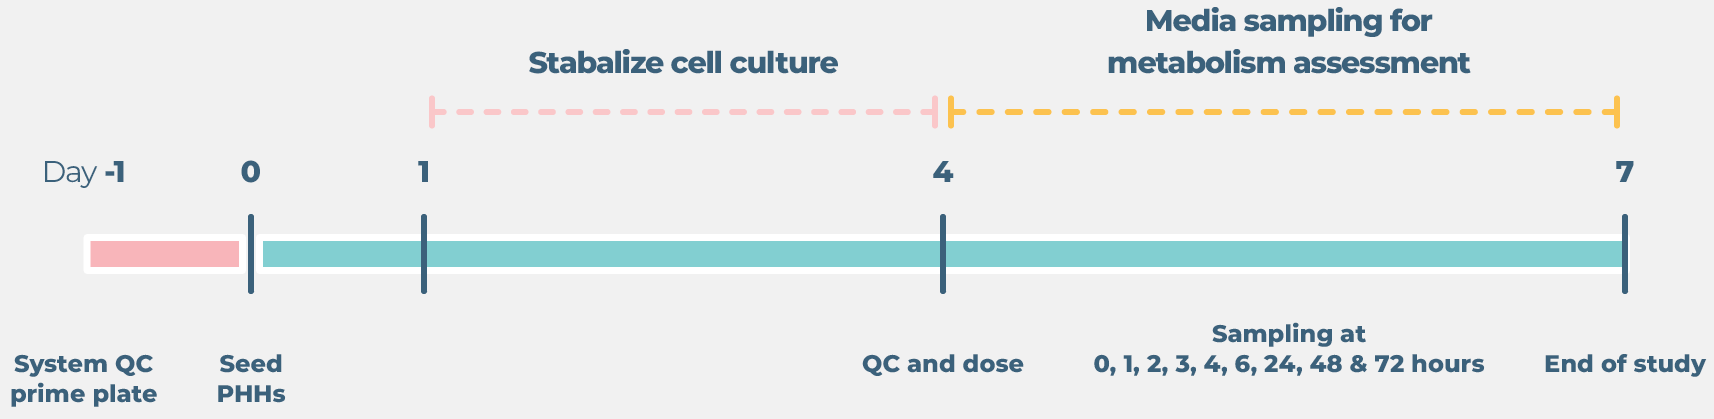

Standard liver drug metabolism cell culture timeline

Image Credit: CN-Bio